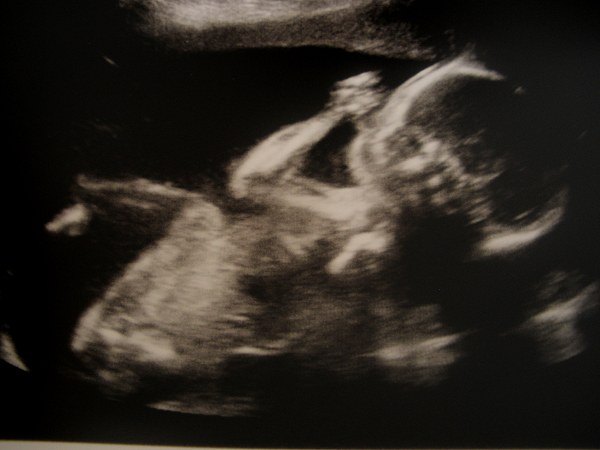

De to første er fra MD, hvor jeg var 20+